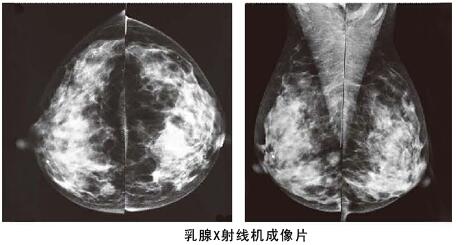

其实相比乳腺彩超,利用数字化钼靶乳腺机对于乳腺管较细或者乳腺本身存在问题,可以进行更加细致检查,而且它是女性乳腺癌早期诊断的金标准,数字化钼靶乳腺机可以发现0.1毫米的钙化点,提示癌前病变。是各种乳腺疾病检查的必备医疗设备:如乳腺炎症,乳腺增生,乳腺纤维瘤,乳腺囊肿等。对于一些年龄较大的女性来说,数字化钼靶乳腺比乳腺彩超检查更加的准确。